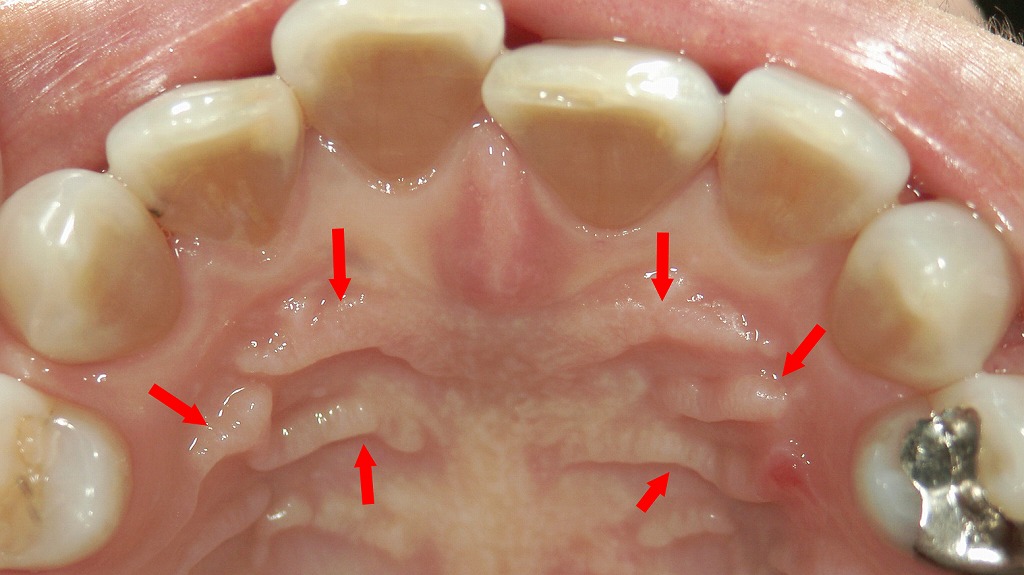

この写真は、上顎の口蓋(上あごの天井部分)を写したもので、赤い矢印が示しているのは 「口蓋皺壁(こうがいすうへき)」 と呼ばれるヒダ状の構造です。

口蓋皺壁は前歯のすぐ後ろに左右対称に並んでいる隆線で、個人差が大きいものの誰にでも存在する生理的な構造です。

この画像に見える「口蓋のヒダ」は、食べ物を飲み込みやすくしたり、発音を助けたりする大切な構造です。総入れ歯を作るときには、このヒダの形をしっかり再現することで、外れにくく、噛みやすい入れ歯になります。